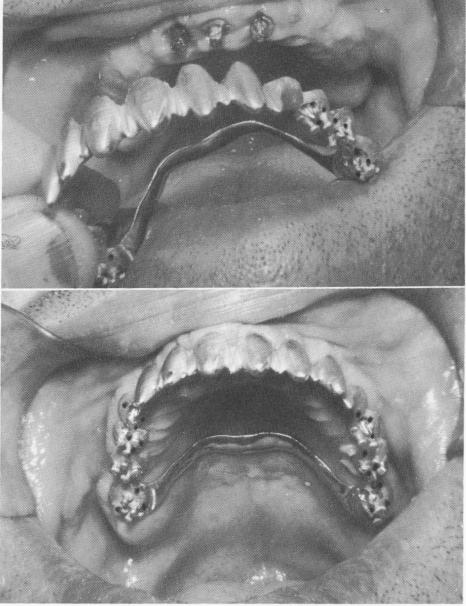

Three anterior vent-plants were screwed into the alveolar bone (Fig. 10-231), and an elastic impression was taken of the entire maxilla, including the three implant shafts (Fig. 10-232). (A full mouth plaster index including the three protruding implant shafts   with or without interchangeable gold copings —could also have been taken.)

Fig. 10-235. The template was fitted into position.

Fig. 10-236. Pin implants were then drilled through the template.